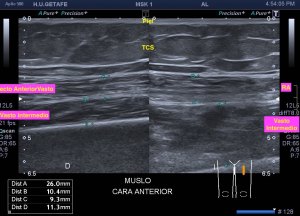

Cuando hacemos una Ecografía para descartar una tendinopatía, lo primero que tenemos que conocer es la normalidad.

El tendón ecográficamente es por definición hiperecogénico. Bajo esta premisa, sí yo observo un tendón hipoecogénico tengo que empezar a sospechar.

1. Anisotropía que ya sabemos que es el cambio en la ecogenicidad del tendón debido al ángulo de insonación o la colocación de la sonda.

Angulando lo más paralelo al tendón posible. Sí es necesario taloneamos la sonda con nuestra mano.

Estirando el tendón siempre para explorarlo correctamente. Posicionamos al paciente para esto.

Otra cuestión que nos hace sospechar tendinopatía es el aumento de tamaño del tendón. Esto lo podemos valorar mediante una exploración comparativa con el lado sano.

Si aparece dolor local siempre será un punto a favor para nuestro estudio y tener la certeza de que los hallazgos enlazan con la clínica.

En resumen, tendremos tendinopatía sin hallemos:

Hipoecogenicidad

Aumento de tamaño

Tendinopatía Aquiles. Aumento de tamaño e hipececogenidad

Tendinopatía rotuliana. Aumento de grosor e hipecogenicidad.